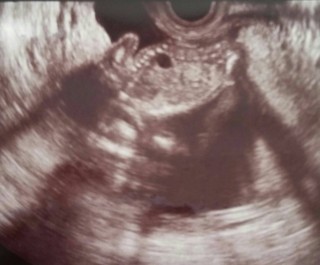

15wのエコーですが。 順調との事で一安心(^。^) なにやら不敵にニヤッとしてます笑